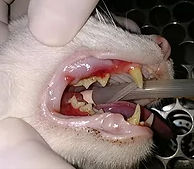

Lesão de

Reabsorção Dentária

Também conhecida como lesão absortiva odontoclástica felina, é uma doença caracterizada por lesões erosivas do esmalte ou cemento, frequentemente situada na porção cervical do dente e classificada de acordo com origem e grau de acometimento, desde lesões superficiais em cemento e dentina, até a exposição pulpar e destruição completa da coroa dentária.